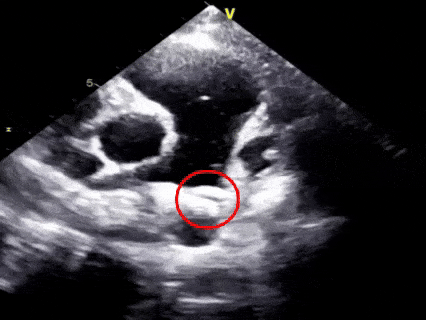

二“扣”,双盘扣合

超声下可见右盘面展开后盘面骑跨在肺动脉与主动脉两侧

三“锁”,成型锁定

多切面确认封堵器形态良好,一侧在肺动脉一侧在主动脉

锁定后超声评估

胸骨旁主动脉短轴切面示封堵器稳固贴合,无残余分流

牵拉试验封堵器整体稳定,盘面无形变,判断已成功锁定